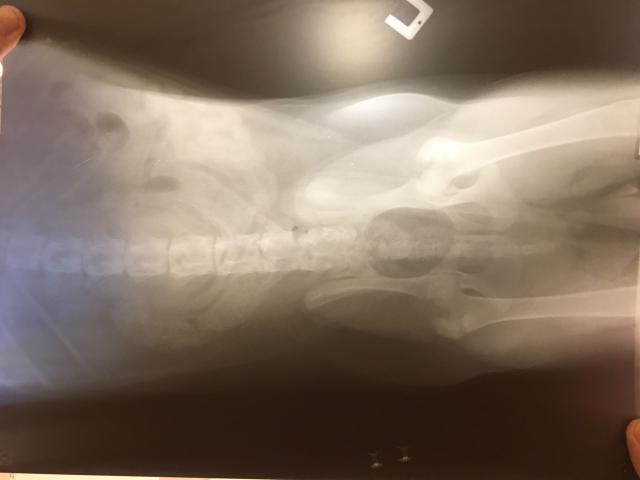

Здравствуйте! у нас щенок спаниеля сейчас ему 7 месяцев. 1,5-2 мес назад он резко заболел. А именно: вечером был вялым , а с утра начал тягать задние лапы пока не расходится, отказался от еды( на него это ну никак не похоже). Не стали медлить и побежали к ветеринару. Он сказал что у нас парез и видимо его просквозило. температуры у собаки не было, анализ крови сдали. далее прокололи ему витамины группы б, дексаметазон, около 4 дней. после приема препаратов ситуация стала повторяться , обратившись к тому же ветврачу нам дали ответ что ему просто нужно попить минералов, купили. Дальше решили обратиться все таки к другому врачу. Его диагноз - дископатия. И у одного и у другого врача спрашивала не дисплазия ли это, ответ-нет. Вообщем начали лечение дургими препаратами,их прикреплою ниже. практически месяц давала ему преднизолон, сималджекс раз в три дня, 10 дней кололи витамины. по истчению и отмены лекарств собака далее начала снова тягать лапы.. сейчас сделали рентген, даем активет 2 т в день. я ношу его гулять по ступенькам на руках ,пытаюсь обеспечить полный покой , но щенок активный под препаратами. Я уже не знаю правильно ли мы его лечим или калечим всеми этими препаратми. Хотелось бы дополнить ,что пару раз брали его за горонд в 4 -5 мес где он бегал гулял целый день, также щенок любил спрыгнуть со всей силы на диван, на стул, со стула..Очень надеюсь на хоть малейшее предположение . Ах да , советовали делать миелографию но у нас в городе такого нет, ни кт , ни мрт. ближайший около 10 часов от нас, с собакой это нереально.